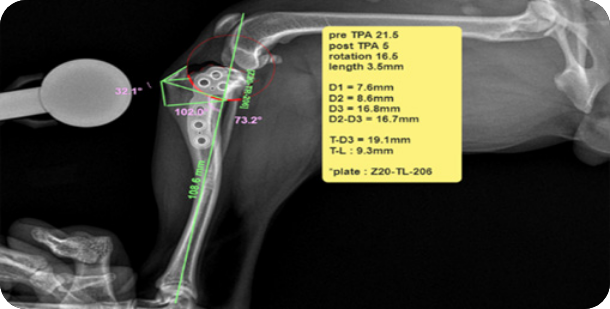

• 전방십자인대 파열(TPLO)

• 수술(TPLO)